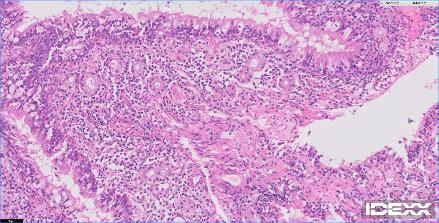

12歳の猫が2週間前よりふらつき、食欲不振、硬直性の痙攣があるとのことで、主治医から紹介がありました。MRIでは前頭葉を中心としたMASSエフェクトを伴う病変が確認されました。リンパ腫あるいは髄膜腫が強く疑われました。CSFでは無色透明で髄液蛋白60mg/dl、Ph8.5 細胞数2(5以下正常)単核球100%パンディ反応(+1)。CSF中のGlu63mg/dl、CK<10、Na 166 K 2.9 Cl 131。手術までの1週間の間にステロイドを中心とした内科療法を実施したところ、臨床症状も改善し、再度、実施したMRIでも以前の病変がほぼ消失していました。ステロイドに強く反応したことからリンパ腫の存在が強く疑われました。今後、化学療法を継続するか?否か?あるいはFIPなどの鑑別を行うために、嗅球と前頭葉の生検が行われました。生検の結果、コロナウイルスの感染、リンパ腫の存在は否定されました。また、血清学的にもトキソプラズマ、FIPの関与は否定的でした。そのため、プレドニゾロンを継続し、経過観察中です。2017年に猫のMUOについて世界で初めてイギリスより16例のまとまった報告が初めての論文として掲載されており、今回の患者さんはそのFMUOのカテゴリーに分類されると考えられました。